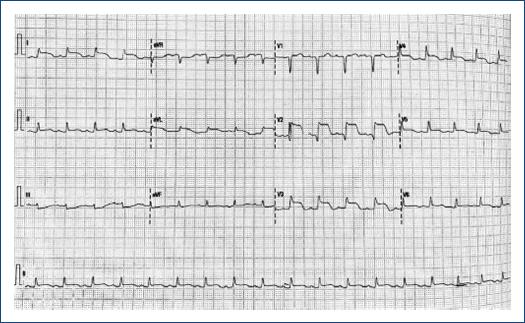

A 75-year-old female with a lymphoma record, diabetes mellitus 2, and hypertension, was hospitalized in another institution with a diagnosis of urosepsis; she required vasopressor treatment and a 3rd generation cephalosporin 2 weeks ago with a partial clinical improvement; but two weeks later she returned to the same hospital with dyspnea and peripheral edema. At the physical examination highlights general rales and peripheral edema, an electrocardiogram (ECG) showed sinus rhythm with ST-segment elevation in V2-V6, DI, and aVL. The troponin I level was 620 ng per liter on a high-sensitivity assay, and she was referred to our institute. Upon her arrival to the emergency department at our insistution, she had a Glasgow score of 10 points, respiratory distress and medium blood pressure <65 mmHg. The ECG persists with a ST-segment elevation in V2-V6, DI, and aVL (Fig. 1). The patient was intubated and required invasive mechanical ventilation, we started anti-ischemic treatment and vasopressor. In the context of ST-segment elevation myocardial infarction and cardiogenic shock, she was transferred to the cardiac catheterization laboratory, where it was reported the absence of injuries in the right coronary, circumflex, and anterior descending arteries (Fig. 2). With anterior and inferior akinesia, and apical dyskinesia, suggestive of Takotsubo cardiomyopathy (Fig. 3). After that, she was transferred to the coronary care unit where the diagnosis of cardiogenic shock was integrated. We iniated treatment with an inodilator (levosimendan) and inserted an intra-aortic balloon pump (IABP) as a ventricular-assistant device. A transthoracic echocardiogram was performed, reporting basal hypokinesia, apical akinesia. LVEF 12%, without a dynamic obstruction of the left ventricular outflow tract and a lung ultrasound with a B-profile. Urine and blood culture were negative; she presented a clinical improvement, so the vasopressor and inodilator were retired and started deflating the IABP. We performed another echocardiogram obtaining a LVEF 27%. As she presented clinical improvement as the days went by, we removed the ventricular assistant device. Unfortunately, in a sudden way, the patient started with ventricular tachycardia requiring pharmacological, electrical defibrillation, and resuscitating maneuvers without a response.